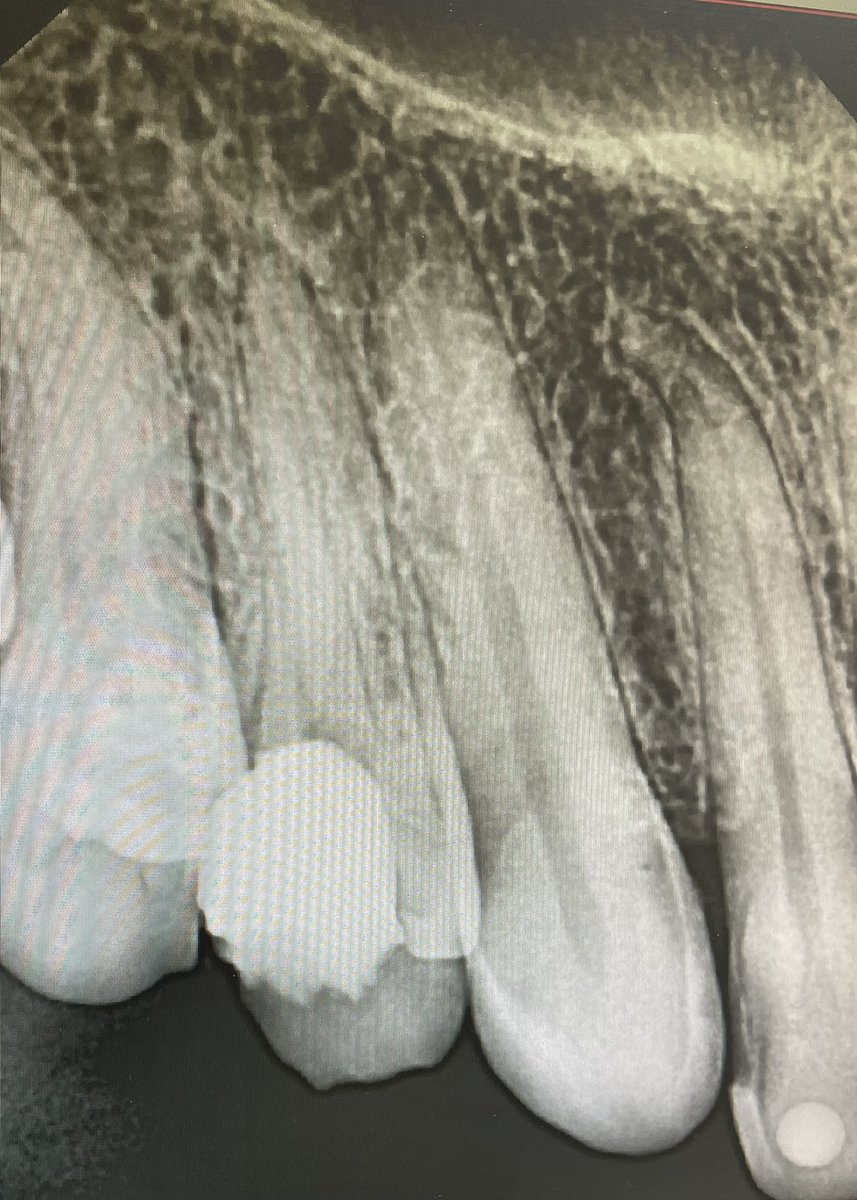

Previously initiated #14 with asymptomatic apical periodontists

RCT was done and post space for future core and crown

Thanks for dr.dowaa